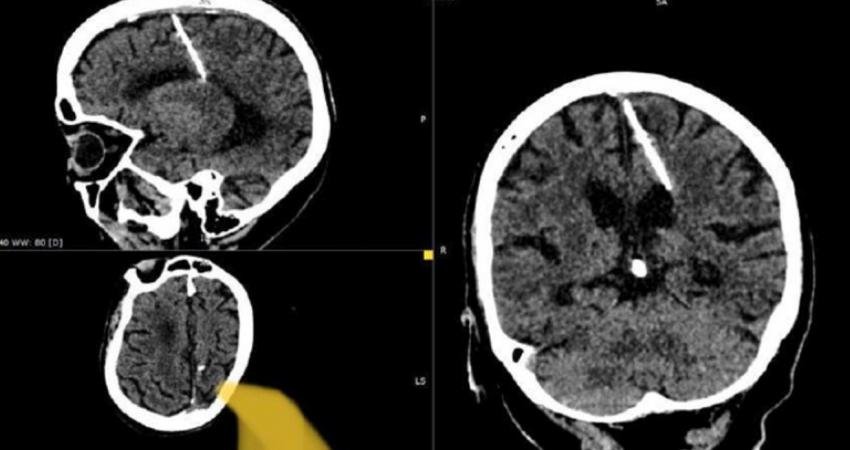

Bu tuhaf vaka, bu ayın başlarında Rusya’nın uzak doğu bölgesinin açıklarındaki uzak bir ada olan Sakhalin’deki yerel sağlık yetkilileri tarafından bildirildi. Doktorlar, bu iğne ile ilgisi olmayan bir CT taraması sırasında kadının beyninde 3 santimetrelik iğneyi keşfettiği bildirildi. İğnenin görüntüleri sağlık bakanlığının Telegram sayfasında paylaşıldı.

Sağlık bakanlığının belirttiğine göre iğne muhtemelen 1943’teki doğumundan hemen sonra kızın ebeveynleri tarafından batırılmıştı. Trajik bir şekilde, 2. Dünya Savaşı’ndan etkilenen bölgelerde yiyecek kıtlığıyla karşı karşıya kalan aileler, bazen özellikle bu yöntemi kullanarak bebeklerini öldürmeyi seçiyordu. İğne beynin fontaneline (bebeğin başındaki yumuşak nokta – bıngıldak) batırılıyordu ve bu delik daha sonra hızla kapanarak eyleme dair her türlü kanıtı ortadan kaldırıyordu. Yerel sağlık departmanı yaptığı açıklamada, “Yıllar süren kıtlık sırasında bu tür vakalar nadir değildi” dedi.

Şaşırtıcı bir şekilde, parietal lobuna yerleştirilen iğneye rağmen kadın hayatta kaldı. Dahası, yaralanma sonucu ciddi sağlık sorunları yaşamamış, hatta baş ağrıları bile yaşamamış gibi görünüyor. Ve şu anda herhangi bir tehlikede olduğu düşünülmüyor. Sağlık bakanlığının açıklamasına göre, iğneyi çıkarmaya çalışmanın kadına gerçekten zarar verebileceği ihtimalini göz önüne alarak, ilgili doktor kadının durumunu izlemeye karar verdi.